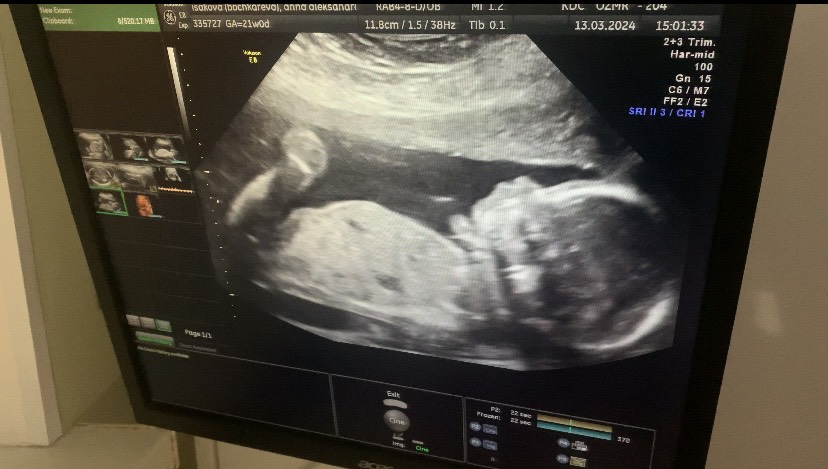

Всем привет❤️ Позади второй скрининг, время летит просто молниеносно. Завтра экватор, 20 недель💫 Самочувствие прекрасное, животик растет, в разы больше, чем был в первую Б. Шевеления чувствую с 16 недель, сейчас уже прям постоянно и отчетливо видно через живот🥰 Все супер, но одно но - это вес. Я стала очень много набирать🤯 на данный момент уже +6кг, меня это очень печалит. Отеков я не замечаю. Но ем я конечно больше, чем до. Хотя питание чистое. Видимо остается только смириться и делать все возможное, чтоб не разожраться :( А по поводу скрининга, все идеально, человек уже 330 грамм, плясала опять на протяжении всего узи😁 В тысячный раз подтвердили нашу принцессу👧🏼🩷 Фотки не дали, но дали снять видео, делюсь скринами) Недель в 28 пойду платно на 4д узи. А пока ходим, наслаждаемся положением и стараемся не разжираться🥲😁